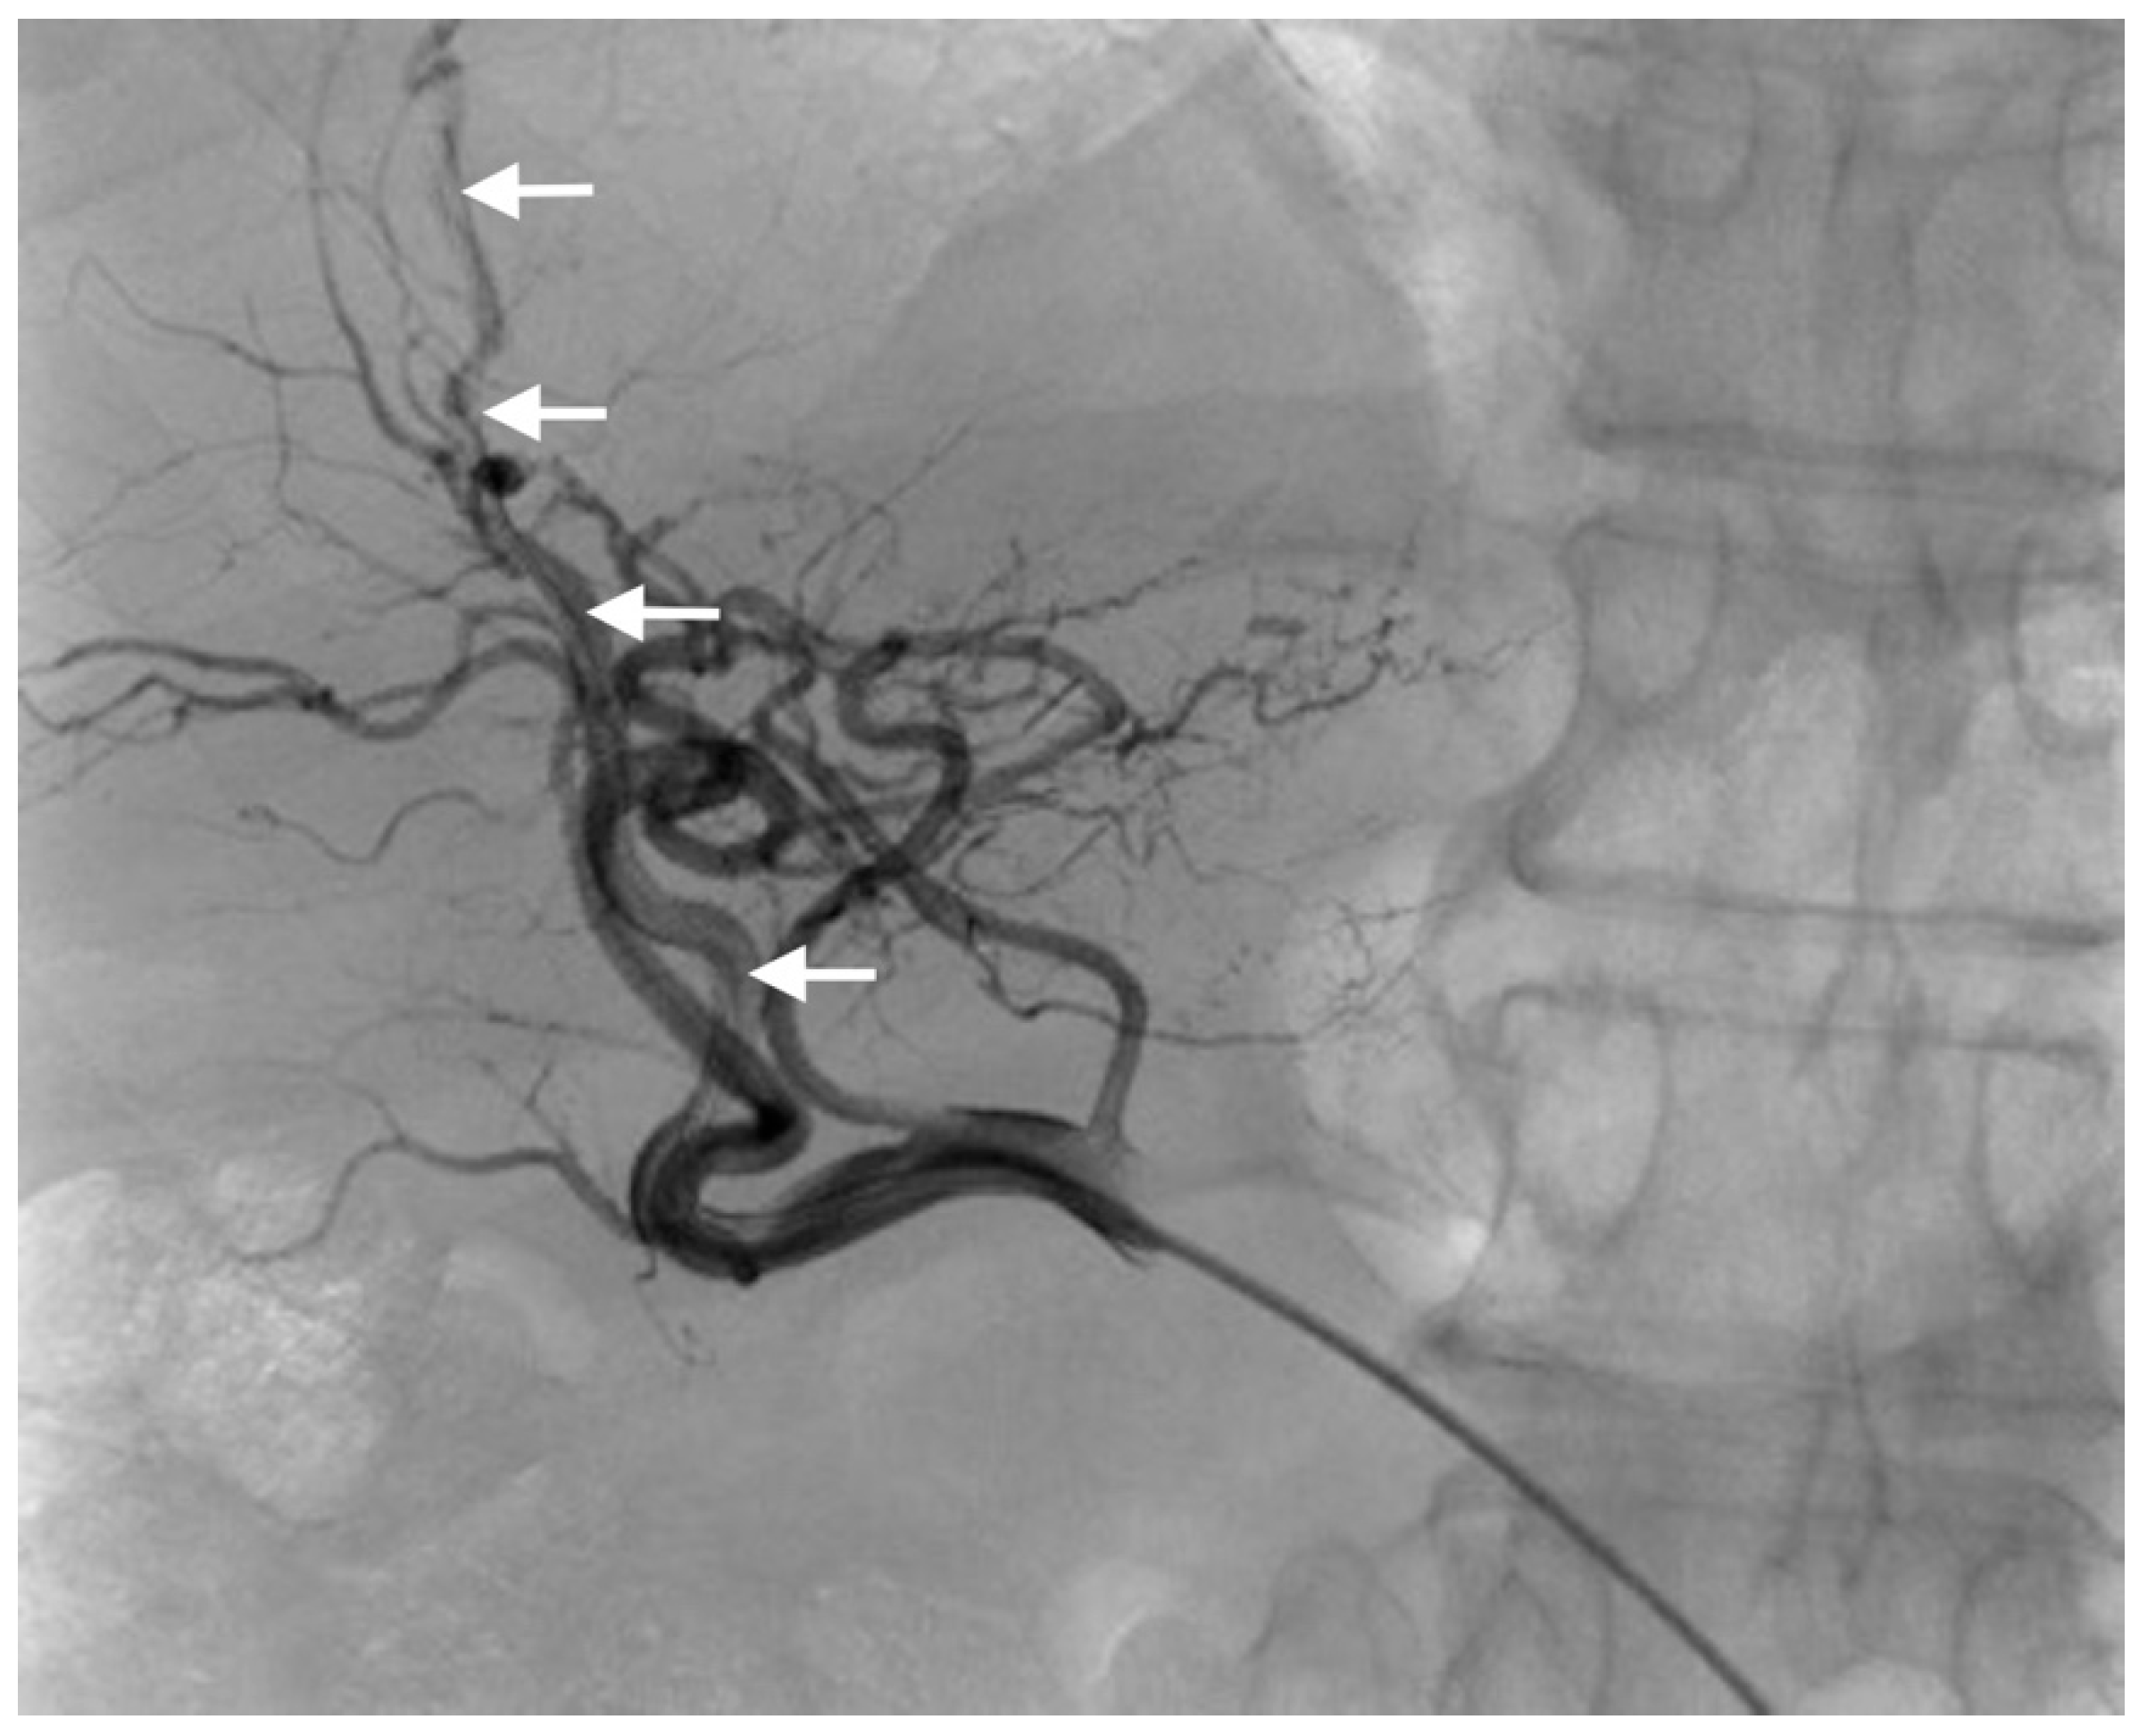

2.2. Percutaneous Microcatheter-Port System Implantation

3.2. Primary Technical Success

3.3. Complications